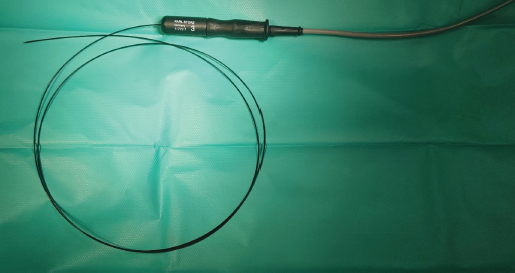

One-and-a-half month after the diagnosis, surgery using monopolar electrocautery was performed. For that, we only needed a semirigid Karl Storz monopolar coagulating ball electrode (3 Fr × 53 cm), LED Surtron 120 high-frequency electrosurgery unit in a monopolar mode, and a grounding steel plate prepared with a thick ultrasonographic gel layer in contact with shaved patient’s skin (Figs. 3-5).

Fig. 4. Semirigid Karl Storz monopolar coagulating ball electrode (3 Fr × 53 cm) connected to a monopolar 4 mm Ø HF connection cable.

Fig. 5. A semirigid Karl Storz monopolar coagulating ball electrode tip.